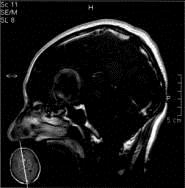

病历摘要:??患者男性,56岁,因右侧视力下降伴视野缺损2个月来院就诊,诉头痛,无明显头晕,无视物重影,无恶心呕吐,无肢体抽搐,无肢体乏力,胃纳佳,大小便...

问题 病历摘要:??患者男性,56岁,因右侧视力下降伴视野缺损2个月来院就诊,诉头痛,无明显头晕,无视物重影,无恶心呕吐,无肢体抽搐,无肢体乏力,胃纳佳,大小便正常,既往史无特殊,入院检查:神志清楚,言语清楚,体毛分布正常,左侧视力4.6,右侧视力4.0,粗侧右颞侧视野缺损,左侧正常,颈软,四肢肌张力正常,肌力正常,病理征(-)。 对于动脉瘤,下列那些是翼点入路的适应症?提示:该患者采用左侧翼点开颅夹闭动脉瘤

选项 A.颈内动脉-眼动脉动脉瘤 B.大脑前动脉动脉瘤 C.前交通动脉动脉瘤 D.颈内动脉末端动脉瘤 E.大脑中动脉动脉瘤 F.后交通动脉-颈内动脉动脉瘤 G.基底动脉末端动脉瘤

答案 ABCDEFG

解析 ABCDEFG